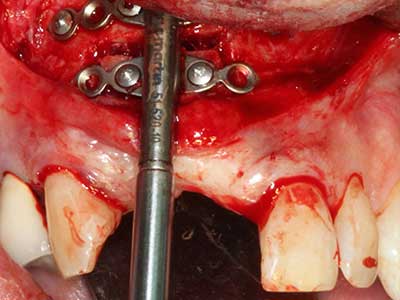

Knochengewebe ist nicht nur rein mineralisch, sondern auch in wesentlichen Anteilen aus Kollagenfasern aufgebaut. Dies gewährleistet neben einer guten Druckfestigkeit eine gewisse Flexibilität, welche für die Durchführung von Augmentationen genutzt werden kann. Bei der klassischen Expansionsplastik im Sinne eines Bone Splittings wird der atrophierte Kieferkamm in seiner Längsachse gespalten und nach Erreichen einer ausreichenden Osteotomietiefe vorsichtig aufgedehnt (Abb. 13-16), idealerweise ohne den Kiefer wesentlich zu deperiostieren (Brugnami, Caiazzo et al. 2014, Stricker, Fleiner et al. 2014). Bewährt haben sich Schrauben- und Plattensysteme mit zunehmender Expansionsdistanz, um die beiden Knochenlamellen unterhalb der Bruchschwelle voneinander zu distanzieren. In der Regel werden Restknochenbreiten von mindestens 3-4 mm gefordert (Chiapasco, Zaniboni et al. 2006), um eine ausreichende Flexibilität und knöcherne Bedeckung der einzubringenden Implantate zu gewährleisten. Ggf. kann eine ein- oder beidseitige vertikale Entlastungsosteotomie die Flexibilität verbessern. Als Alternative zur klassischen Technik wurde eine Kombination mit weiteren augmentativen Techniken vor allem auf der bukkalen Seite beschrieben.

Mittels Piezosägen erfolgt die Anlage des Splittings besonders schonend und ohne wesentliche Dimensionsverluste, so dass sich keine signifikanten Unterschiede von Implantaten im gesplitteten Kiefer im Vergleich zum nicht defizitären Alveolarkamm gezeigt haben (Chiapasco, Zaniboni et al. 2006, Danza, Guidi et al. 2009). Gerade beim lokal begrenzten und tiefen Splitting ist jedoch stets auf eine ausreichende Wasserkühlung zu achten, um thermische Belastungen in den apikalen Osteotomiebereichen zu vermeiden.